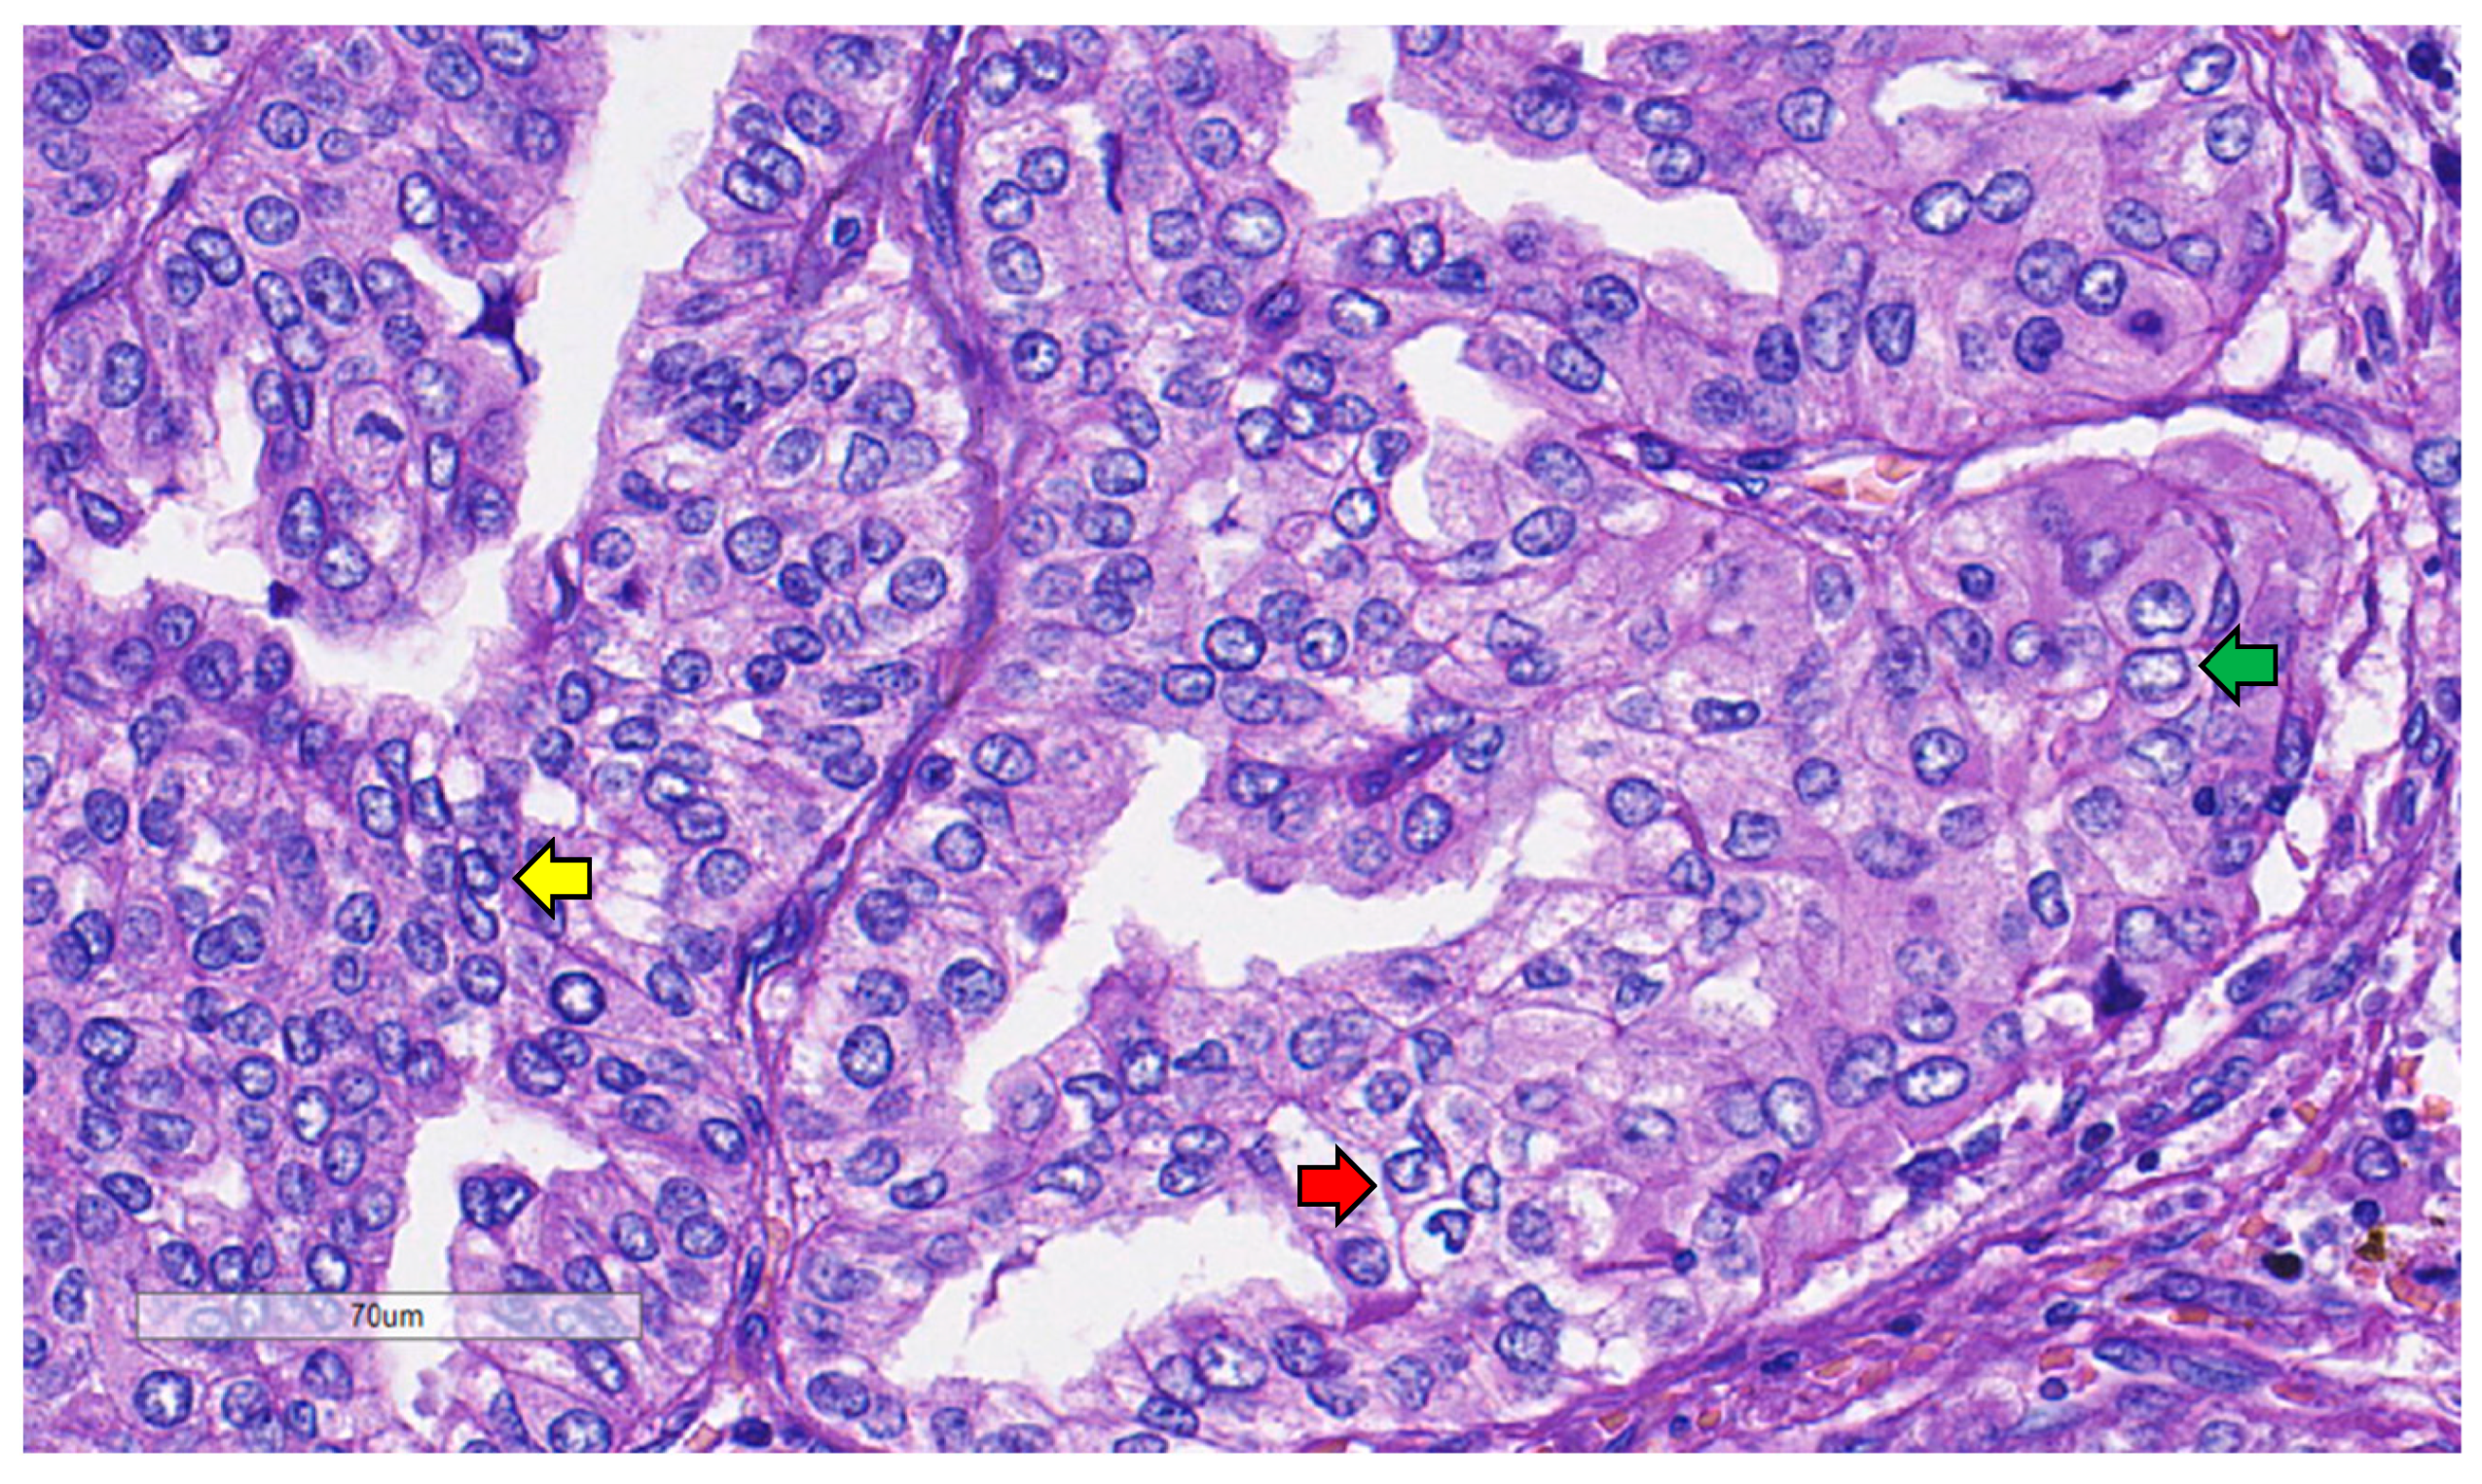

3.2.2. Mitosis

3.2.3. Growth Pattern

3.2.4. Nuclear Features